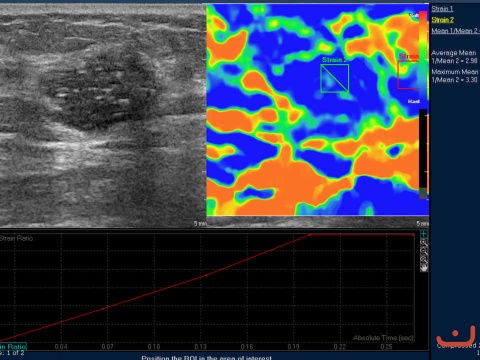

Case 45-E1

Malignant solid mass

Friday, 22 May 2015

161.21 KB (480 x 360 px)